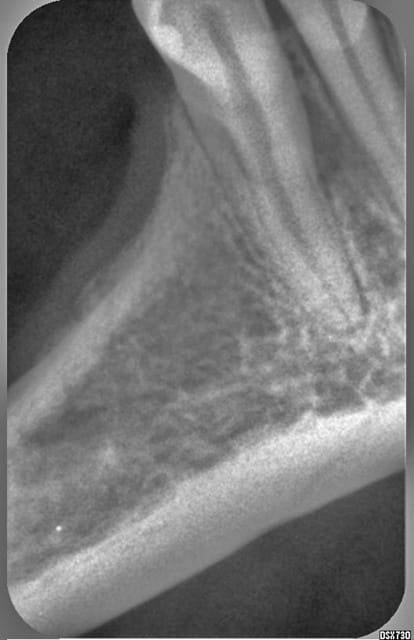

17082007 synnio - Eugenol

une deuxieme racine?